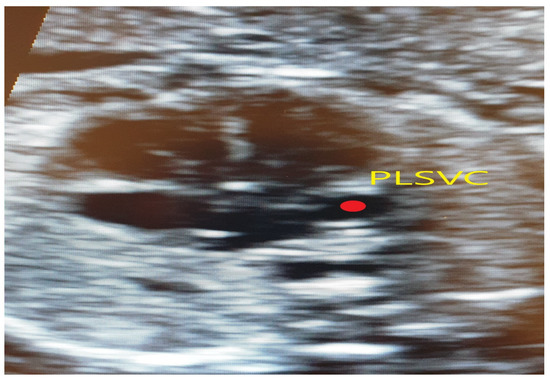

4.2. Case 2

4.3. Case 3

4.4. Case 4